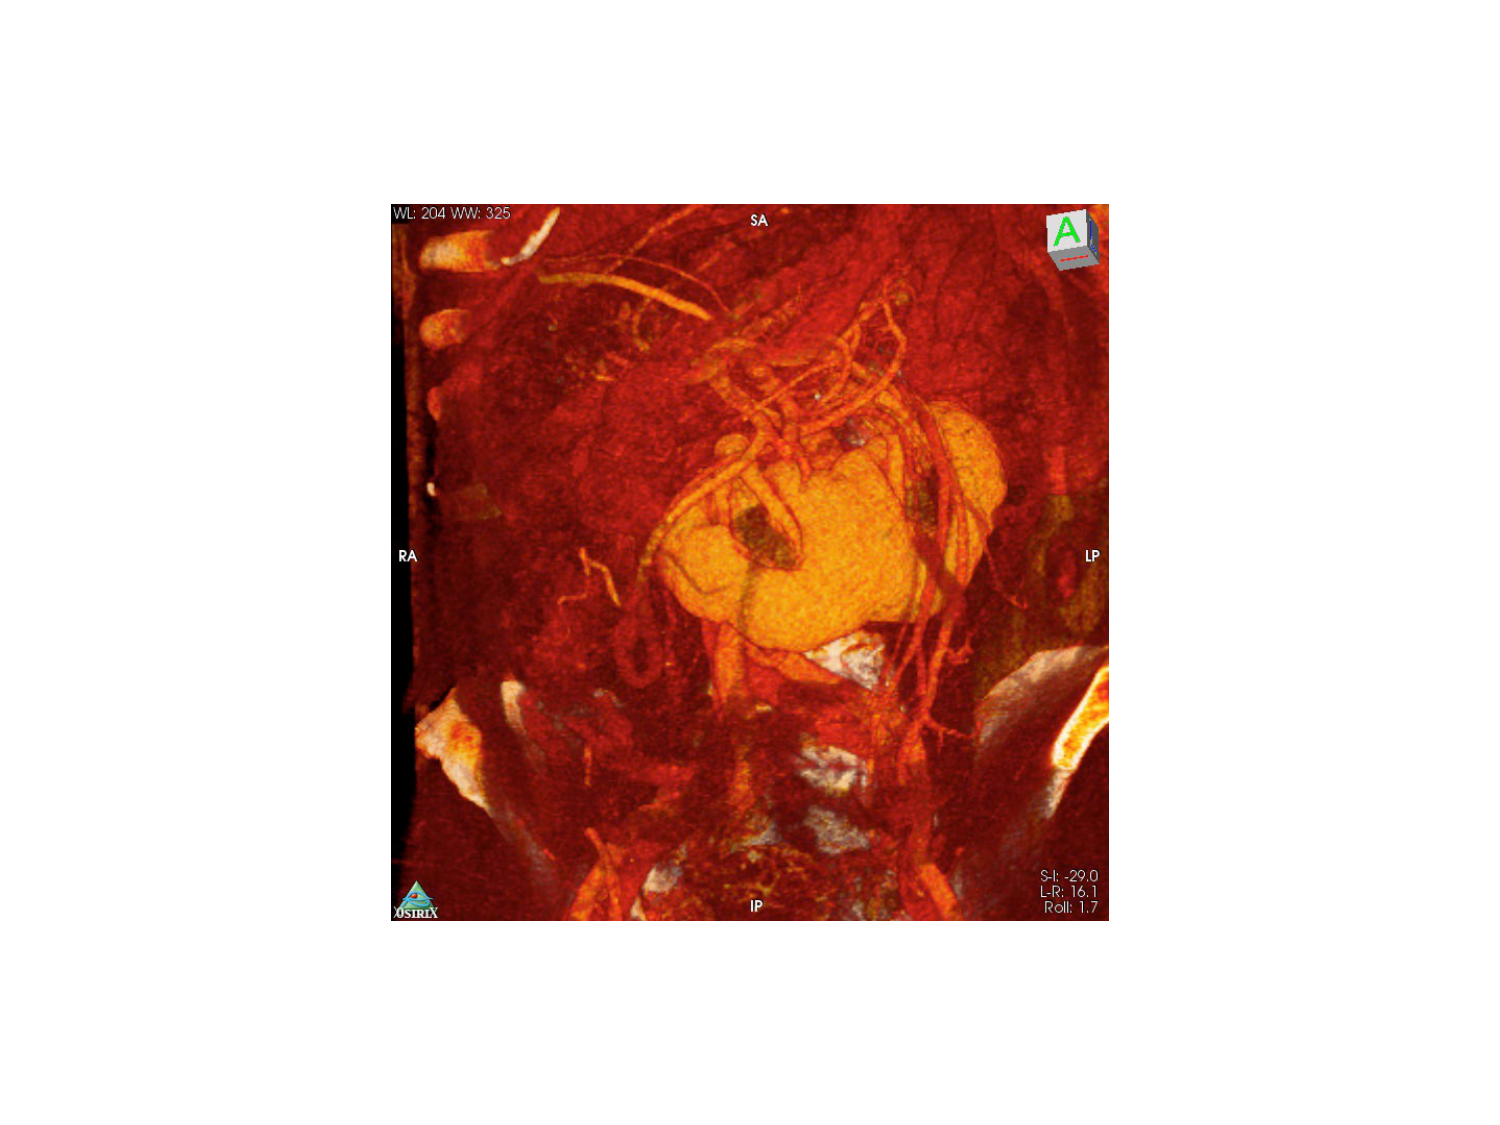

11.47 · Rein, voies urinaires et retropéritoine

Rein, voies urinaires et retropéritoine